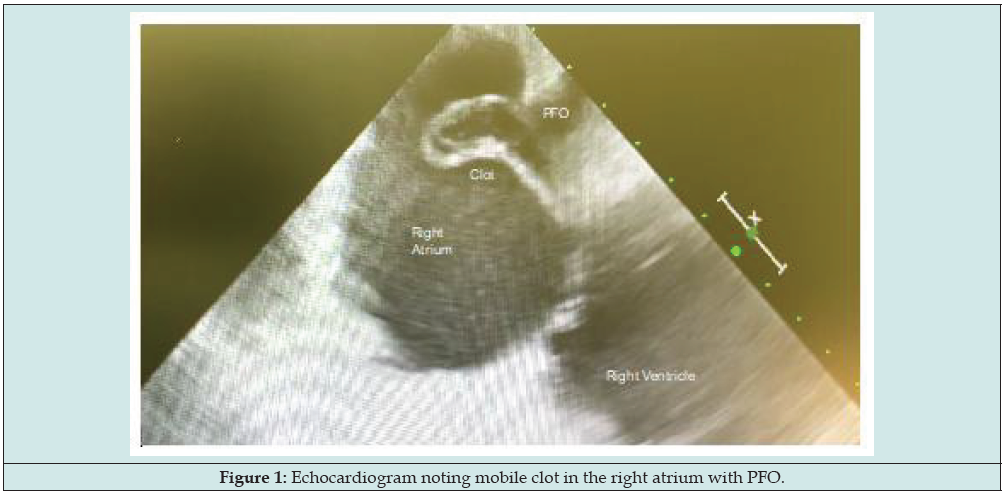

Figure 1: Echocardiogram noting mobile clot in the right atrium with PFO.

48-year-old female presented with dyspnea and fatigue. CT imaging found pulmonary embolus. Echocardiogram noted biatrial thrombus extending through mitral and tricuspid valve, as well as through a patent foramen ovale (PFO) (Figures 1 & 2). She underwent emergent sternotomy, embolectomy of left and right atria, left and right pulmonary arteries, and atrial septal defect closure (Figure 3). She progressed well post-operatively and was discharged on postoperative day 7 on therapeutic anticoagulation. Three year follow up, alive and no complications from the procedure.

48-year-old female presented with dyspnea and fatigue. CT imaging found pulmonary embolus and a heparin drip was initiated. She later developed chest pain which led to an echocardiogram. This imaging noted biatrial thrombus extending through mitral and tricuspid valve, as well as through a Patent Foramen Ovale (PFO) (Figures 1 & 2). She underwent emergent sternotomy and was placed on cardiopulmonary bypass. The left and right atria were explored, and a mechanical embolectomy performed of both the left and right atria and left and right pulmonary arteries. After complete removal of the clot, the atrial septal defect was closed with a pericardial patch (Figure 3). She was weaned from bypass and had no immediate complications. She progressed well post operatively and was discharged on postoperative day 7 on therapeutic anticoagulation. Three year follow up remains healthy and without complications of this procedure.